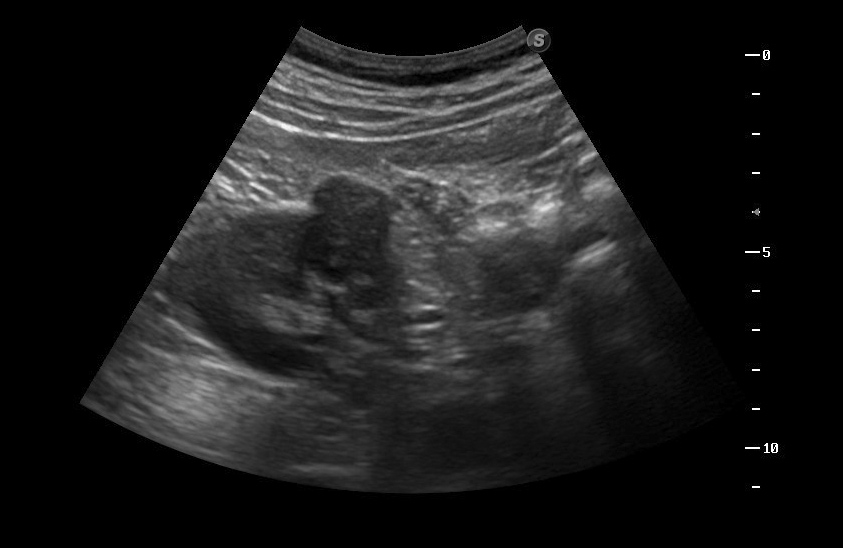

Образование в правой почке

Мужчина средних лет.Жалоб не предъявляет.

С его слов, 10 лет назад в правой почке находили кисту.

Сканер Sonoscape S40

гипоэхогенное образование в среднем сегменте, деформирующее контур почки...наверное рак

Ответ каунасских радиологов - киста почки.

Что-то на узи на кисту не похоже...

В том то и дело. Но тем не менее - это киста, анамнез уже несколько лет.besliu писал(а):Что-то на узи на кисту не похоже...

Динамики нет, на последнем видео четко видна киста при включенной 2й гармонике